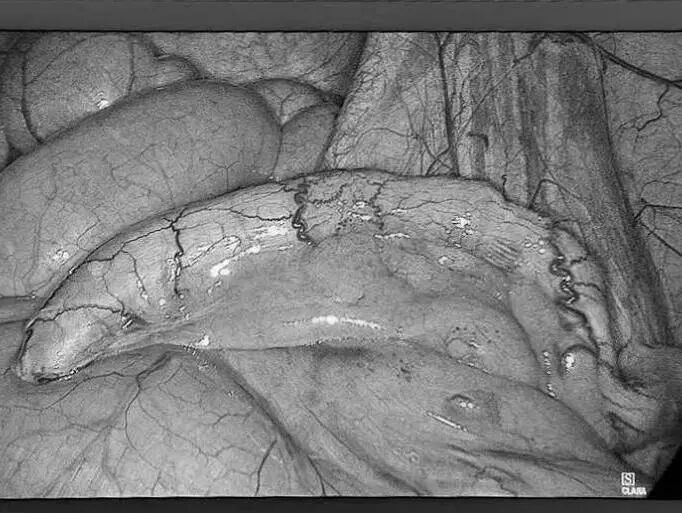

近日,贵州航天医院普外科开展了“呵护生命,你我相伴”第二届肿瘤患者联谊会。这场别开生面的联谊会,为肿瘤患者提供了一个相互支持、相互鼓励的平台,收获了大家的一致好评。 会上,普外科联合中医科、临床营养科组成专家团队,就肿瘤相关的科普知识、发病因素、治疗手段、护理方法、营养指导、造口护理、术后中药治疗和注意事项等内容进行了深入浅出的讲解。 副院长廖江荣致辞 普外科主任梁跃发言 健康讲座 在交流互动环节,患者及家属们踊跃发言,提出了在治疗与康复过程中遇到的各种问题与困惑,医护人员耐心为患者及家属答疑解惑,提供了切实可行的指导与帮助,让大家获益良多。 此次活动开展,让这些患者在与病魔抗争的过程中不再感到孤单与无助,进一步增强了他们在康复之路上的信心和力量。未来,贵州航天医院普外科将继续秉承“关爱患者、守护生命”的服务理念,与患者携手共进,在抗癌这条充满挑战的道路上坚定前行,为更多肿瘤患者照亮生命的希望之光。 贵州航天医院普外科专家团队 梁 跃 普外科主任 主任医师 临床擅长:对普外科各类肿瘤手术具有丰富的临床经验。 毕业于遵义医学院,遵义市医学会小儿外科学分会常务委员,遵义市肛肠协会理事,遵义市医学会核医学分会(第二届)委员会委员;荣获第三期“黔医人才计划”优秀学员称号;主持市级课题1项,完成省级课题1项,在国内各类刊物上发表论文10余篇。 钱科洪 普外科 副主任医师 临床擅长:从事普外科临床工作30余年,对各类普外科疾病的诊治、乳腺、甲状腺、胃十二指肠、结直肠等疾病及疑难杂症具有丰富的临床诊疗经验。 贵州航天医院普外科简介 基本情况 贵州航天医院普外科成立于1968年,前身属于航天部O61基地3417医院外一科,1998年3417医院、3427医院合并后更名为普外科,下设胃肠外科、肛肠外科2个亚专业科室,拥有在全市较为先进的专科设备和技术,是中国疝病专科联盟单位,贵州医科大学附属医院胃肠外科专科联盟单位。开放床位40张,配备医护人员21人。 专科特色 普外科致力于胃肠及肛肠疾病的外科临床诊治及科研,以腹腔镜微创外科技术为本,形成以快速康复治疗胃肿瘤、结直肠肿瘤、小肠肿瘤、直肠脱垂、肥胖病、急腹症、各类疝、痔、瘘等专科特色,同时注重胃肠疾病尤其是结直肠恶性肿瘤的基础研究和临床转化研究,总体诊断和治疗水平在区域同级医院居于领先水平。 开展手术:腹腔镜下胃癌根治术,腹腔镜下袖状胃切除术,腹腔镜下胃肠道间质瘤切除术,腹腔镜下结、直肠癌根治术,胃癌、结直肠癌的精准治疗,腹腔镜下小儿疝气、成人疝修补术,腹腔镜下阑尾手术,内痔的硬化注射治疗及痔疮的微创治疗:ATH、PPH、TST,直肠脱垂的各种手术治疗,难治性伤口VSD技术,鼻胃肠管、肠梗阻导管置入术,肛肠术后间歇性导尿技术,并引进了中医适宜技术,也为各种化疗患者提供输液港安装,提高患者就医体验。 腹腔镜下腹股沟疝无张力修补术 腹腔镜下腹股沟疝 无张力修补术 腹股沟疝里金斯坦(Lichtenstein)手术 PPH微创术治疗环状混合痔 黏连性或炎性肠梗阻-肠梗阻导管 腹腔镜袖状胃切除 腹腔镜阑尾切除术 腹腔镜阑尾肿瘤切除术 腹腔镜下结肠癌根治术 诊疗范围 胃肿瘤、结直肠肿瘤、小肠肿瘤、肥胖症、各类急腹症、腹部外伤、腹壁疝、便秘、直肠脱垂、痔疮、肛瘘、肛裂等胃肠、肛肠外科疾病。 End